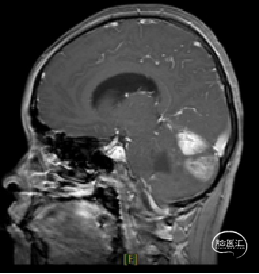

现病史:患者18个月前无明显诱因出现间断头痛,休息后可缓解,开始未予重视,未行特殊治疗。1周前患者无明显诱因出现恶心、呕吐,就诊于当地医院,行颅脑MRI提示:小脑囊实性占位性病变,首先考虑毛细胞星型细胞瘤。现患者为求进一步治疗就诊于我院,门诊以“脑肿瘤”收入院。患者自发病以来神志清,精神可,饮食睡眠正常,二便如常,体重未见明显下降。

术前MRI